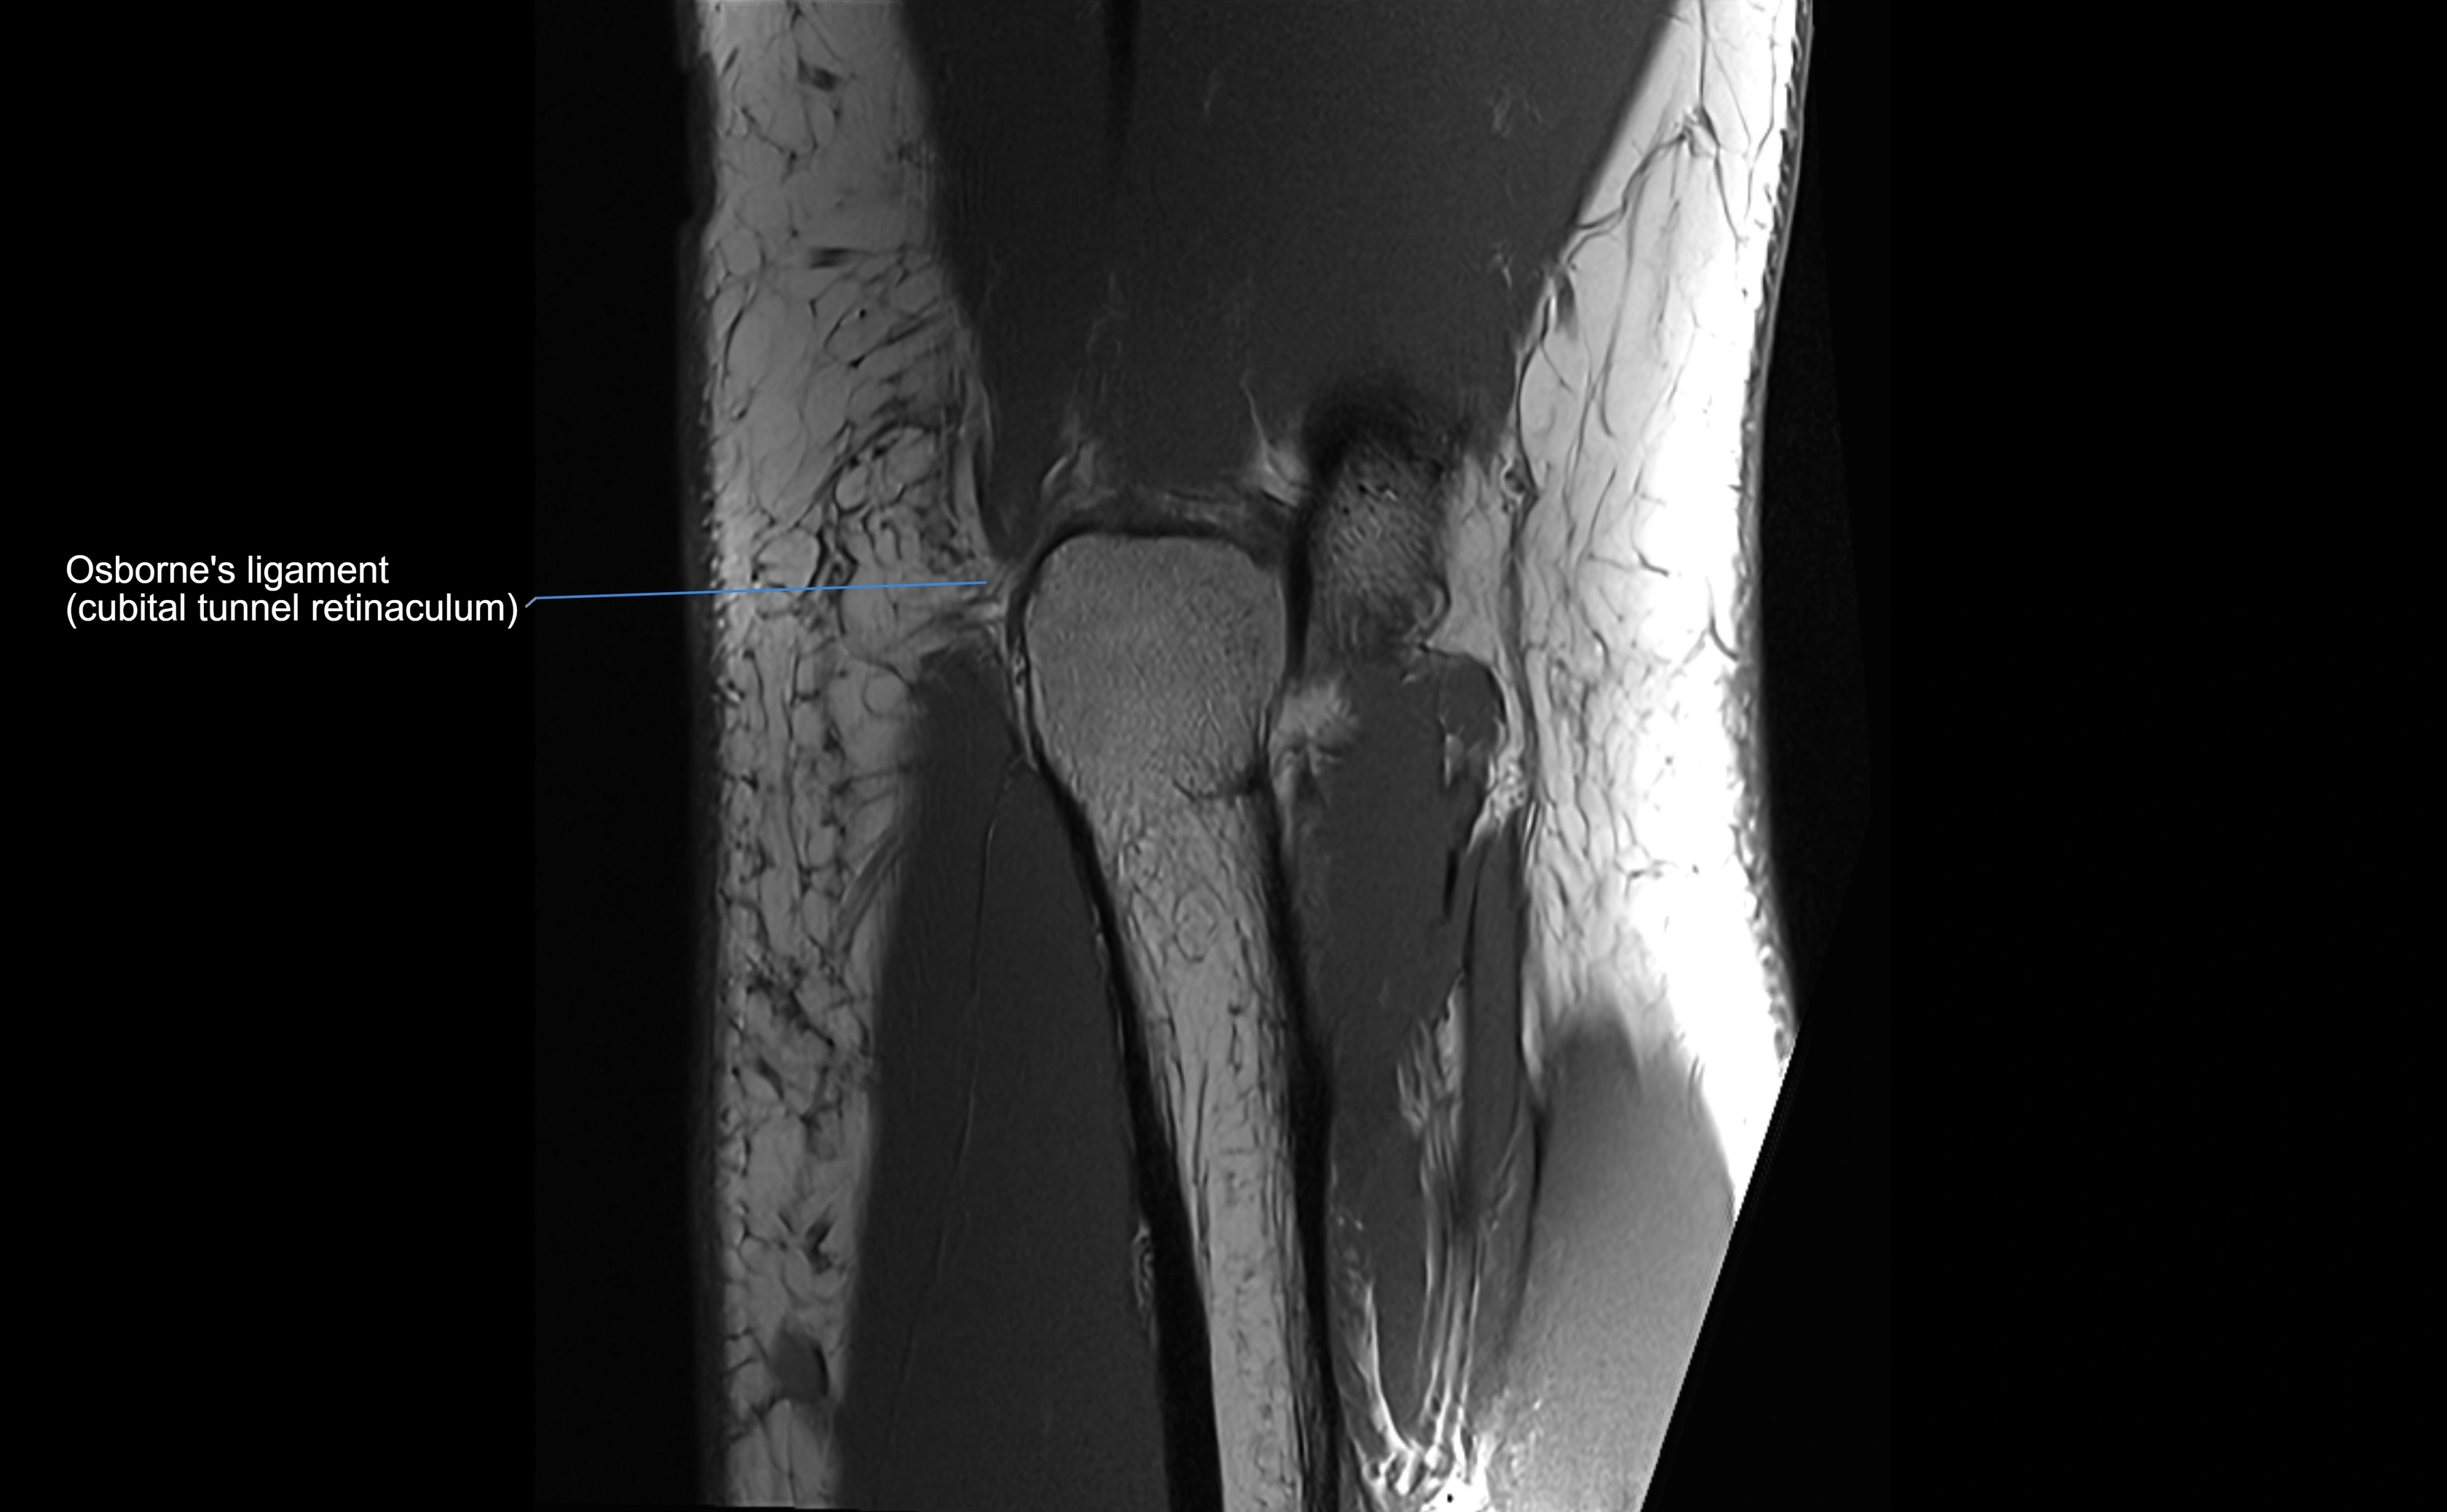

MRI Appearance

T1-weighted images:

• Ligament: low signal intensity (dark), appearing as a continuous band around the radial head.

• Adjacent fat and marrow: bright, creating contrast with the ligament.

• Thickening or disruption indicates injury or fibrosis.

• Joint capsule and synovium seen as thin low-signal lines contiguous with ligament margins.

MRI images

image